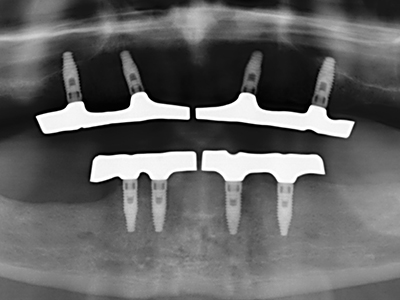

Indication: Preparation near nerves

Indication: Apical resection

When surgical procedures are performed on bone in the immediate vicinity of sensitive structures such as blood vessels or nerves, rotary instruments pose a significant risk of iatrogenic injury. Piezoelectric devices can be helpful for preparation of bone covers and removal of hard tissue close to nerves, particularly for exposure of nerves after iatrogenic injury but also during nerve lateralization for resective and reconstructive procedures or implant placement (Fig. 17-20). Light contact between the piezotip and the nerve does not generally result in damage but proceeding incautiously with saw-like motions or attachments where a residual bone substrate remains may cause temporary or even permanent nerve damage. However, the risk of damage is considered to be substantially lower than when using saws or milling instruments (Pereira, Gealh et al. 2014).